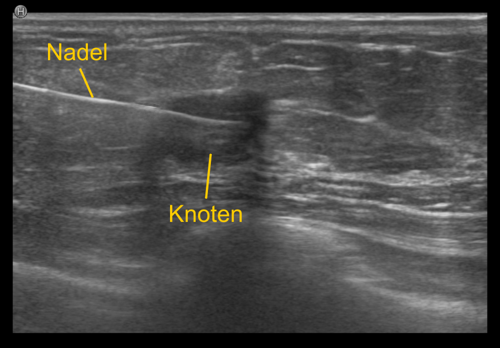

Bei der Gewebeprobeentnahme, der sogenannten 'Biopsie', wird eine dünne Nadel in den verdächtigen Bezirk eingebracht, und eine oder mehrere Gewebeproben entnommen. Diese Proben werden anschließend vom Pathologen aufbereitet und unter dem Mikroskop genau analysiert. Die Entnahmeregion wird üblicherweise mit einem kleinen Markierungsklipp gekennzeichnet, damit die Stelle bei Bedarf jederzeit wieder auffindbar ist.

Die unterschiedlichen Methoden richten sich nach der Bildgebung. Ist die verdächtige Region im Ultraschall sichtbar, wird die ultraschallgezielte Gewebeprobeentnahme bevorzugt, da sie relativ einfach und rasch (üblicherweise zwischen 15 bis 20 Minuten) durchführbar ist.

Sonographiegezielte Stanzbiopsie